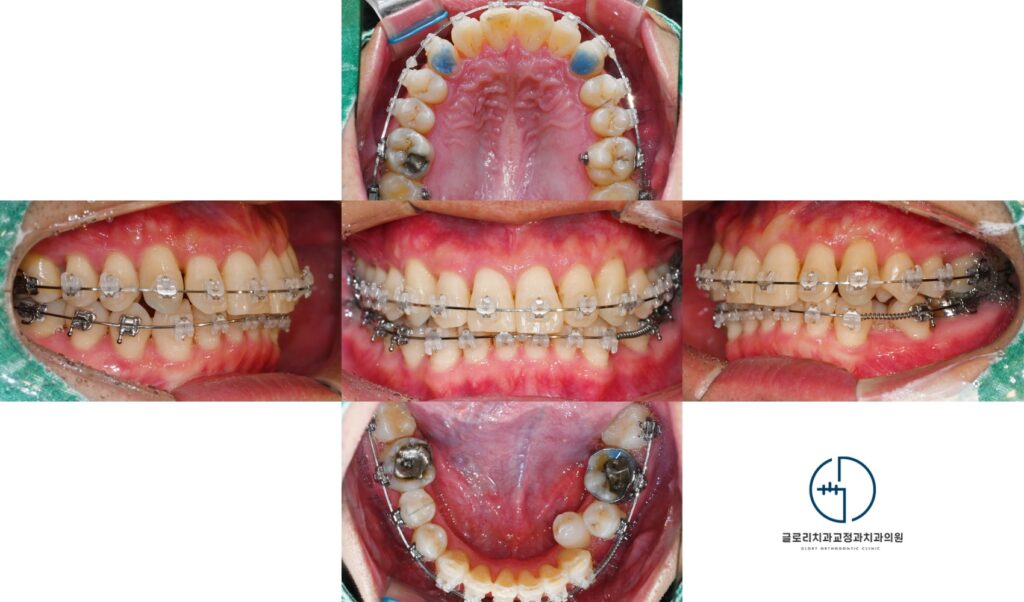

안녕하세요, 망우동 교정 치과 김정은 원장입니다. 전치부는 대화를 하거나 웃을 때 먼저 시선이 닿는 부위로치아의 배열 하남나으로도 얼굴 인상과 심미적…